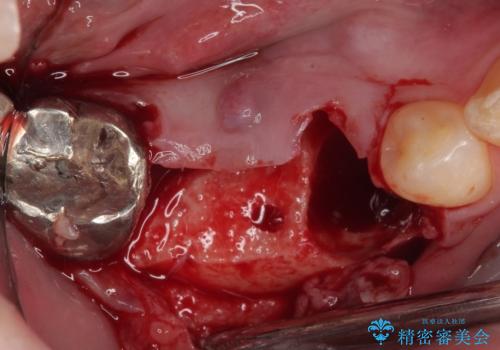

問題が起きていた手前の歯から膿が出てきたことを自覚して当院を来院されましたが、既に歯根破折をしており、抜歯が必要な状態でした。

咬合力が非常に強い患者様であり、2歯欠損のブリッジ(しかも大臼歯は失活歯)は歯根破折のリスクが高すぎると判断し、抜歯部および欠損部に対して、インプラントによる補綴治療を行うこととしました。

抜歯即時埋入部と後方の欠損部は、即日荷重(インプラント埋入と同時に仮歯を装着すること)が可能な安定値が得られましたが、長い期間欠損した状態で過ごすと、欠損部に舌を押し当てる癖が発現してしまい、舌からの側方圧でインプラントが脱離するリスクが著しく高まってしまうため、即日荷重は行いませんでした。